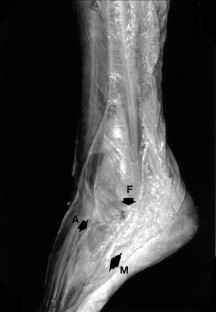

The rich sensory innervation of the ankle and foot is manifest through the numerous communicating branches linking the neural trunks, particularly the superficial peroneal and sural nerves on the anterolateral aspect of the hindfoot. The 35 communicating branches seen in 55 dissections (58%) were proximal in half of the cases, lying in the malleolar and lateral tarsal regions, and distal in the other half, in the metatarsal region. The communicating branch was straight in 25 cases and curved in 11. The average distances of the communicating branch from the crest of the lateral malleolus and the tubercle of the 5th metatarsal was 4.7 and 4.1 cm, but there was a wide range of values. We believe that stretching of the proximal communicating branch during forced inversion of the ankle and/or foot or during fractures of the calcaneus or direct injury in surgical approaches or arthroscopy of the ankle may lead to unexplained pre- and submalleolar pain. Advances in modern imaging may allow recognition of these branches and guidance of infiltration and even neurolysis in cases of failure of conservative treatment.

Fig. 1

Fig. 2

Fig. 3

Fig. 4

Fig. 5

Fig. 6

Fig. 7

Fig. 8